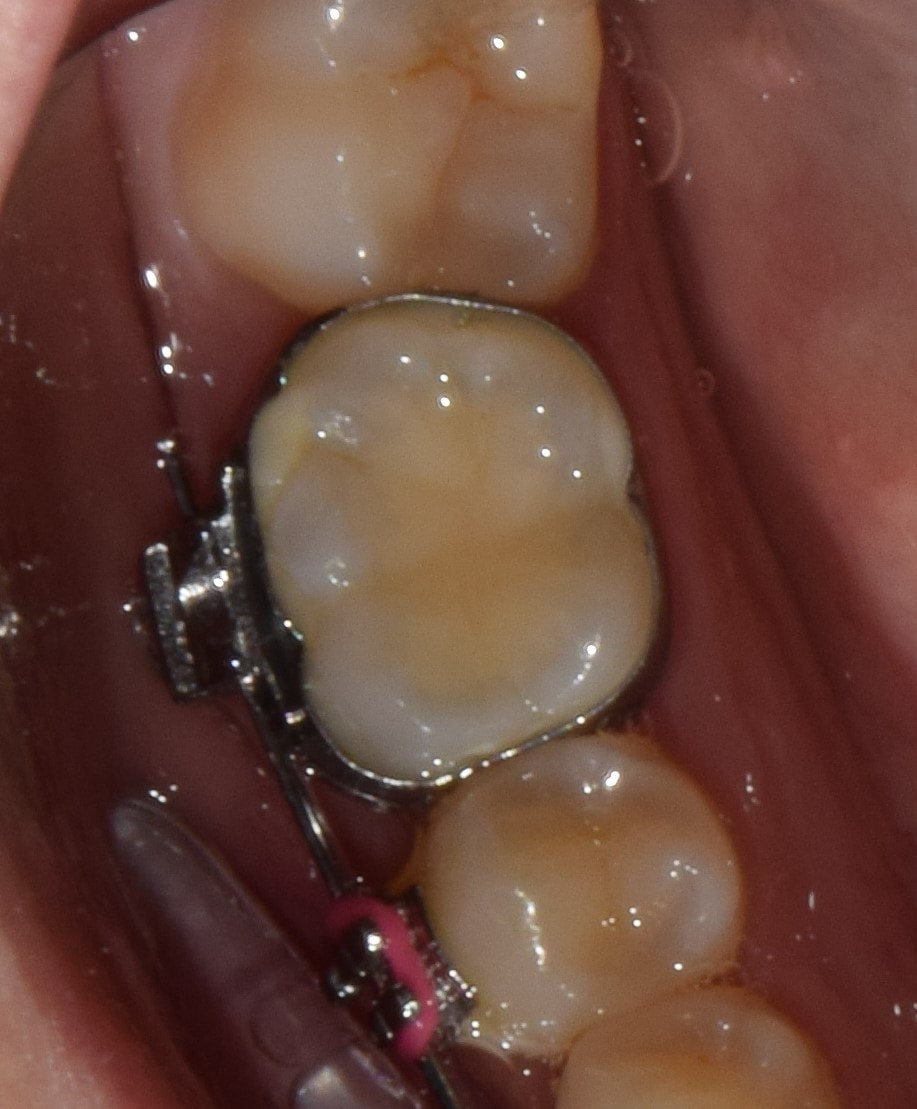

Gyűrű

Általában őrlőfogaknál használt, a teljes fogat körülölelő fém fogszabályzó alkotóelem, melyre tubus van hegesztve. Vannak olyan rögzített (EVA-platte) és kivehető (lip-bumper, Headgear) készülékek, amelyek használatához elengedhetetlen. A fogágyra igen negatív hatással van, ezért használatát minimálisra csökkentettem, de amikor szükséges, jó szolgálatot tesz.